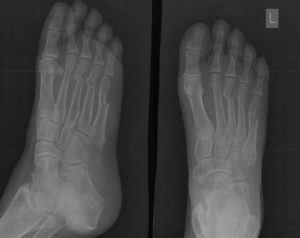

Прицельная рентгенограмма костей предплюсны с указанием на стрессовый перелом.

Рентгенологический метод является одним из наиболее простых в исполнении и дешевых для подтверждения диагноза маршевой стопы.

Однако, часто вначале заболевания (в первые 2-3 недели), проведенная рентгенограмма может стать ложноотрицательной, так как не начались процессы заживления и небольшие трещины, достаточные для беспокойства пациента, невозможно визуализировать.

Если выполнить рентгенологическое исследование в первые недели после физической нагрузки и появления боли, то можно ничего не обнаружить. При типичном переломе повреждается кортикальный слой кости и нередко происходит смещение, что хорошо видно на снимке. Маршевый перелом – это локальное повреждение кости, боль локализуется в центре, наблюдается медленная перестройка ее структуры.

Характерные признаки маршевого перелома на рентгенограмме:

- Участок просветления в виде полосы, расположенной поперек кости – это и есть зона, где в результате перестройки старая ткань не успевает своевременно заменяться новой.

- С первого взгляда на маршевую стопу, может сложиться впечатление, что кость разделена на 2 части, отличающиеся друг от друга своей структурой. Они никогда не бывают смещенными друг относительно друга. Смещение отломков кости – это всегда признак обыкновенного травматического перелома.

- Вокруг участка просветления кость может изменять свою форму и напоминать веретено. Это следствие постоянных регенеративных процессов. Врач, увидев такое утолщение, может расценить его как сформированную костную мозоль – последствие давнего перелома.

Томография является более дорогостоящим, но информативным методом в определении маршевого перелома, поскольку позволяет послойно рассмотреть кость и выявить патологию даже в самом ее центре.